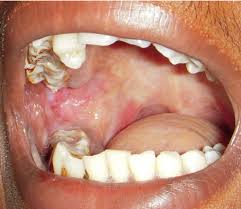

Oral submucous fibrosis is a chronic debilitating disease of the oral cavity characterized by inflammation and progressive fibrosis of the submucosal tissues (lamina propria and deeper connective tissues):

Oral submucous fibrosis results in marked rigidity and an eventual inability to open the mouth.

The buccal mucosa is the most commonly involved site, but any part of the oral cavity can be involved, even the pharynx

Hypovascularity leading to blanching of the oral mucosa, staining of teeth and gingiva, and trismus are major symptoms:

- Oral submucous fibrosis is clinically divided into three stages, and the physical findings vary according:

- Stage 1:

- Stomatitis includes erythematous mucosa, vesicles, mucosal ulcers, melanotic mucosal pigmentation, and mucosal petechia.

- Stage 2:

- Fibrosis occurs in ruptured vesicles and ulcers when they heal, which is the hallmark of this stage.

- Early lesions demonstrate blanching of the oral mucosa.

- Older lesions include vertical and circular palpable fibrous bands in the buccal mucosa and around the mouth opening or lips, resulting in a mottled, marblelike appearance of the mucosa because of the vertical, thick, fibrous bands running in a blanching mucosa.

- Specific findings include the following:

- Reduction of the mouth opening (trismus)

- Stiff and small tongue

- Blanched and leathery floor of the mouth

- Fibrotic and depigmented gingiva

- Rubbery soft palate with decreased mobility

- Blanched and atrophic tonsils

- Shrunken budlike uvula

- Sinking of the cheeks, not commensurate with age or nutritional status

- Stage 3:

- Leukoplakia is precancerous and is found in more than 25% of individuals with oral submucous fibrosis.